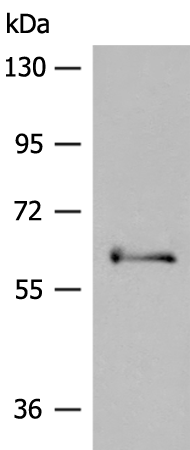

分类: 科研抗体货号: P04420别名: PRKAR1应用: WB,IHC反应种属: Human, Mouse, Rat